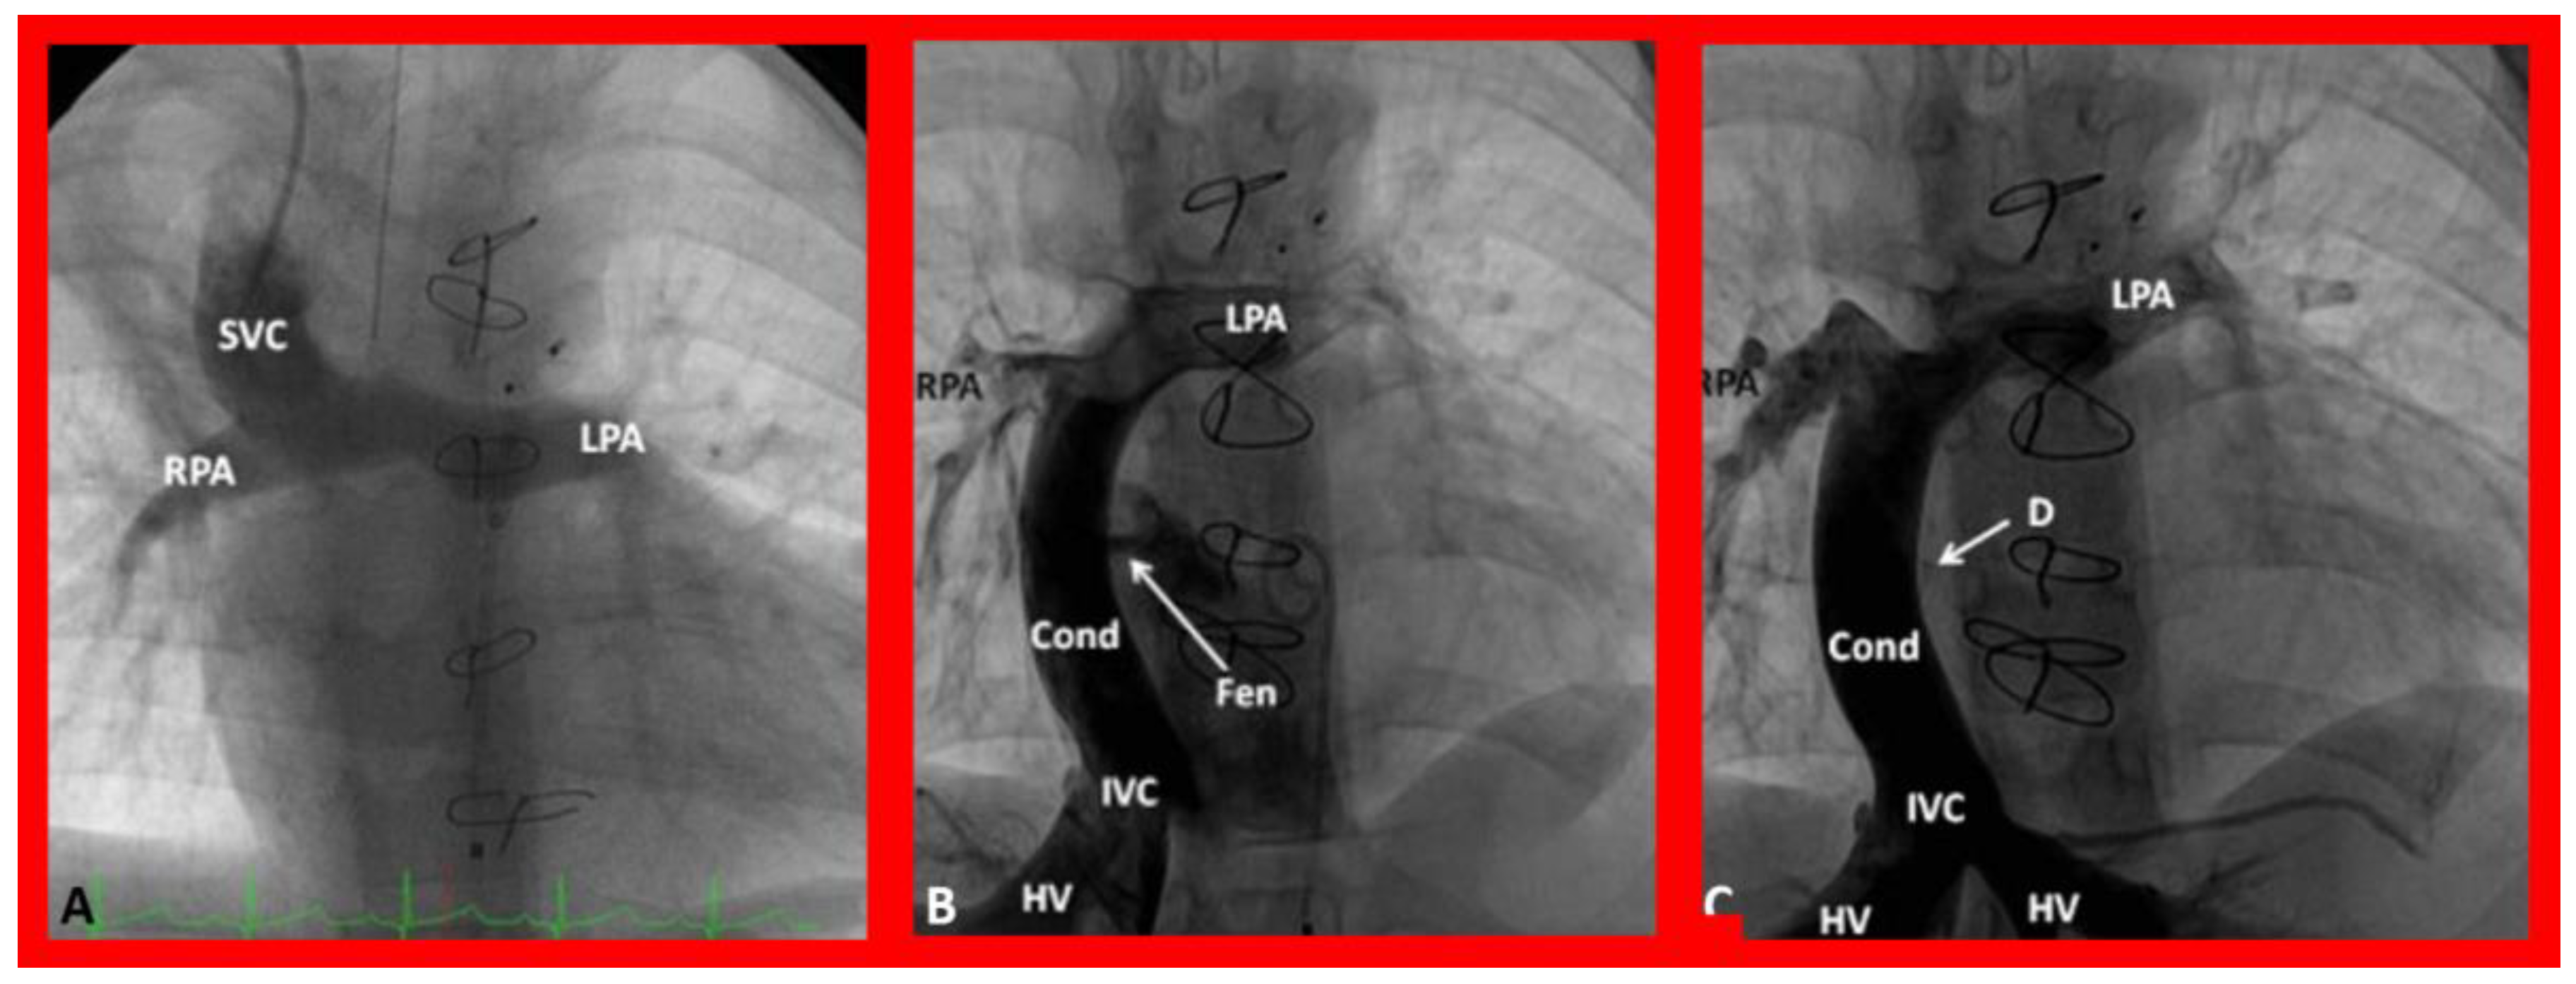

9. Cardiac Catheterization with Angiography, Magnetic Resonance Imaging (MRI) and Computed Tomography (CT)

10.4. Follow-Up after Palliative and Corrective Surgery

11. Summary and Conclusions